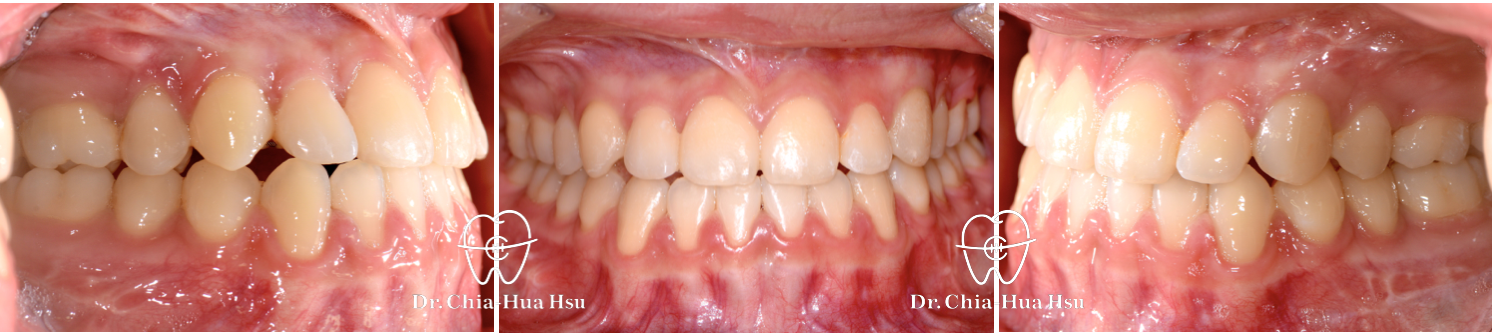

治療前

治療後

• 病患主訴:戽斗、前牙開咬。

• 問題分析:患者是標準的骨骼三類咬合(Skeletal Class III),下巴明顯較長,還有上顎牙弓過窄、開咬以及齒列不正。

• 治療結果:齒列排齊,咬合功能恢復,外觀更和諧。